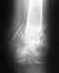

По данным рентгенограммы тазобедренного сустава: "виден медиальный перелом шейки правой бедренной кости (со смещением отомков по длине и ширине)"